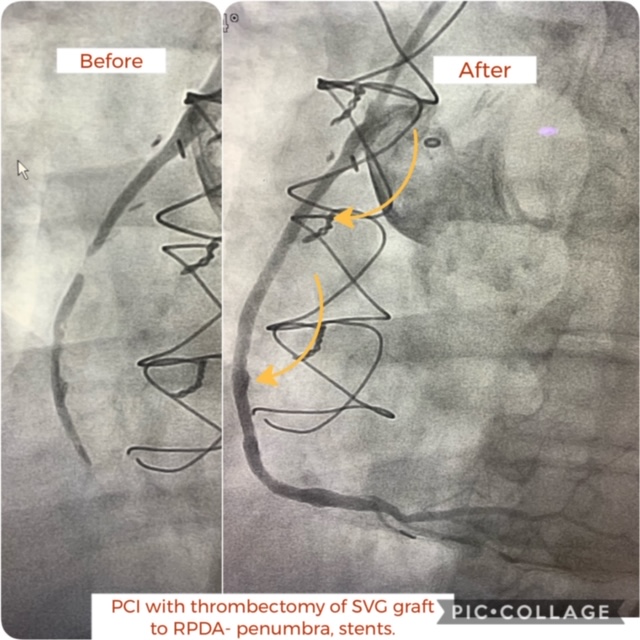

Coronary bypass grafts

Case of the Day – Coronary Bypass Grafts

Coronary bypass grafts are an excellent choice to manage Coronary Artery Disease, however, they are not time-proof. Graft decay and occlusion is a common problem that worsens with time and suboptimal management of risk factors. Treating such a severe disease doesn’t require repeating open-heart surgery. With modern treatment options, the occluded grafts can be treated…